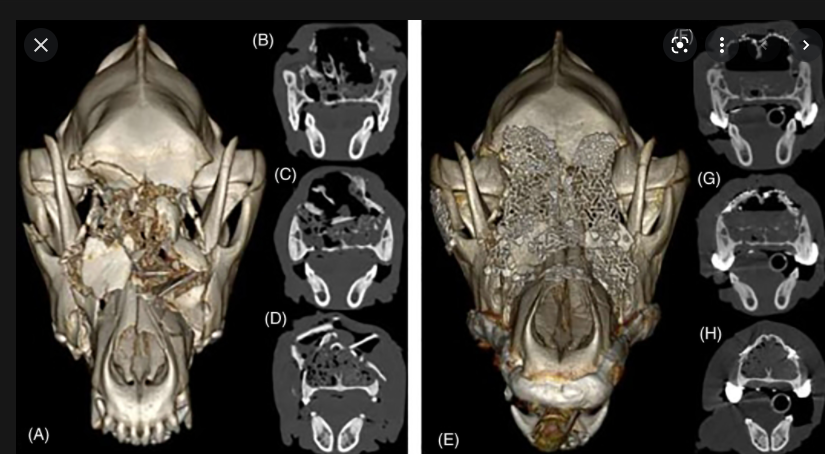

개두술 후 금속 매쉬를 이용한 두개골 봉합 자료, 반려견

무엇을 상상하든 그 이상의 결과물을 만들정도로 최근 의료 기술은 너무도 잘 발달하고 있음.